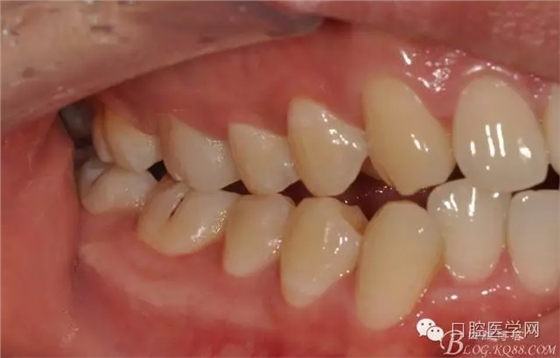

檢查:16近中齲壞深,探痛,已露髓,冷測痛明顯,叩痛(+-),無松動全口牙石(++),牙齦紅腫。

圖3 牙體預(yù)備前頜面觀

圖4 牙體預(yù)備前咬頜觀